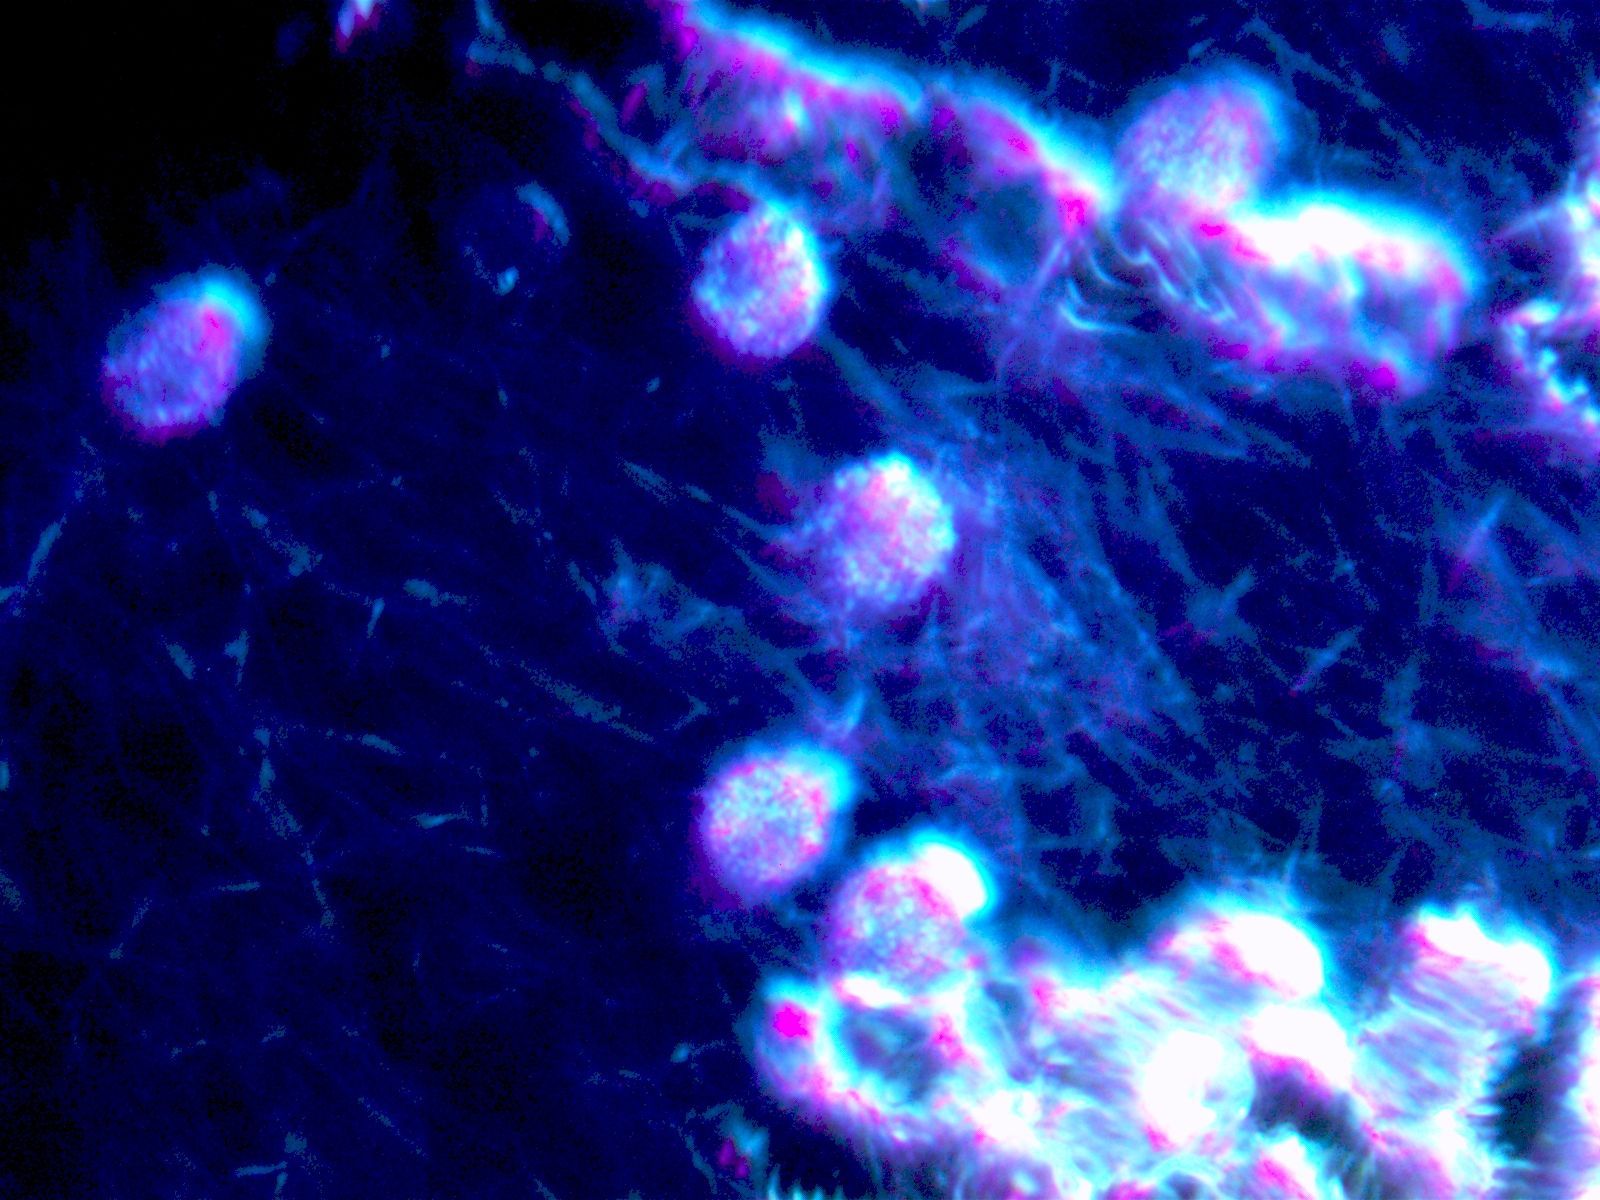

Die Dunkelfeldmikroskopie

Die Dunkelfeldmikroskopie ist eine spezielle Variante der Lichtmikrosokopie. Diese spezielle Untersuchungsmethode des Vitalbluts gibt tiefe Einblicke in die biochemischen Prozesse des Körpers und ist eine ideale Ergänzung, sowohl zu den herkömmlichen schulmedizinischen Laborblutbefunden, als auch zur bioenergetischen Körpermessung mit Global Diagnostics / Vitalfeldtherapie.

Während bei den üblichen Labor-Blutbildern die Bestandteile des Blutes quantitativ bestimmt werden, zeigt das Dunkelfeld Aktionen und Interaktionen der Blutzellen, sowie deren Form und Beschaffenheit. Dies ermöglicht nicht nur Beurteilung von akuten Erkrankungen, sondern auch Dispositionen für gesundheitliche Probleme, bevor sie sich in Symptomen manifestieren.

Zustand und Funktionsfähigkeit der Blutzellen

Aktivität des Immunsystems

Befall mit Krankheitserregern (Bakterien, Viren)

Für die Dunkelfeldmikroskopie genügt ein einziger Blutstropfen aus der Fingerbeere. Dieser wird in Ihrem Beisein über das Dunkelfeldmikroskop analysiert und in Echtzeit zum Mitschauen auf einen Bildschirm übertragen -Bei vorliegenden Belastungen können wir in einem gemeinsamen Gespräch ein grundlegendes Therapiekonzept entwickeln.